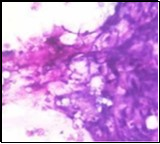

Figure 1.Parachordoma on fine needle aspiration cytology depicting clusters of spheroidal cells with eosinophilic cytoplasm, regular nuclei and clumped, encompassing myxoid stroma 13.

Parachordoma on fine                needle aspiration cytology depicting clusters of spheroidal cells with               eosinophilic cytoplasm, regular nuclei and clumped, encompassing myxoid stroma 13.